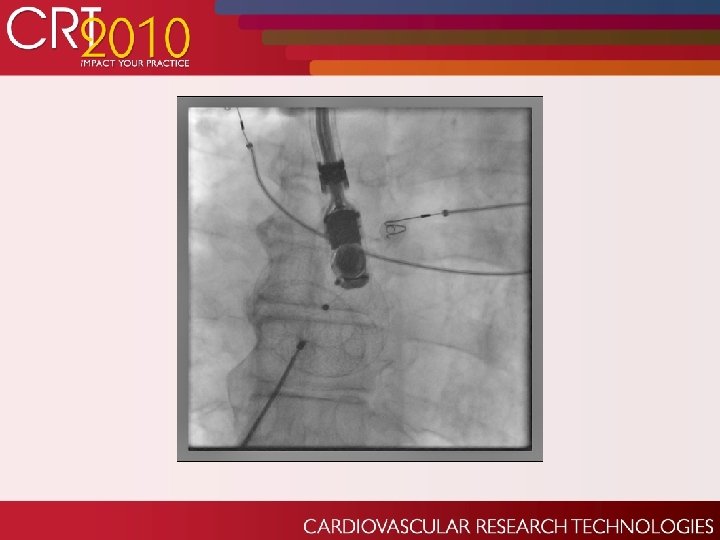

Echo post-procedure:

Later the Same Day…. Though non-emergent CT surgery took patient to OR the same night. Percutaneous extraction considered but concern over thrombus potentional on device sitting in LA so long. Did well post op until day 3.